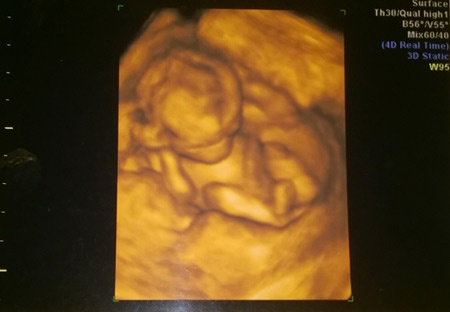

Azért félve mentem a 4D-s ultrahangra, mert hát hallottunk már cifra dolgokat, nem is lepődtem volna meg nagyon, ha pont én leszek az akinek elnézik a gyerek nemét. De hát azért a 16.héten már nagyon jól lehet mindent látni, így a kedves szonográfus hölgy is megerősítette a dokim "diagnózisát", miszerint már tényleg örülhetek, mindenféle félelem nélkül, ez a baba biztosan kislány.

Viszont sztrájkolt a kisasszony, egyáltalán nem lehetett látni az arcát, végig csücsült a pocakomban, megmozdulni nem volt hajlandó, oldalról láttuk csak, sőt egy idő után ezt is megunta, és egyszerűen hátat fordított, és bebújt a méhlepénybe. Tornázhattam, guggolhattam, köhöghettem én amennyit akartam, Őnagysága ugyanabban a pózban volt szinte végig a fél órás vizsgálat alatt. Mondjuk én teljesen megértem, gondolom tiszta anyja már most, ezért nem vehető zokon tőle, ha csak a jóképű dokibácsinak hajlandó megmutatni magát!